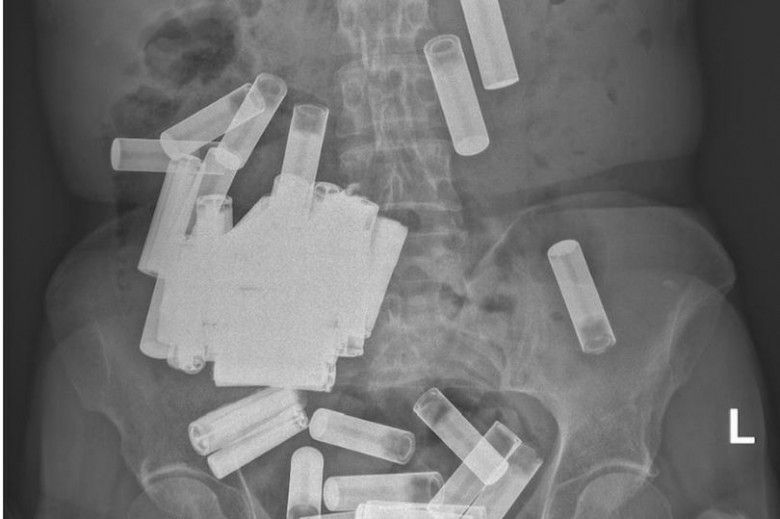

Hasil X-Ray Menunjukkan Banyak Benda Aneh (Daily Star)

Benar saja, setelah dilakukan pemeriksaan X-Ray, tim medis mengidentifikasi adanya benda asing di tubuhnya. Ternyata, benda itu adalah baterai. Tidak hanya satu, tim medis menemukan total 55 baterai di tubuh wanita itu yang tersangkut di area perut dan anusnya.

Beruntungnya, baterai-baterai itu tidak ada yang menghalangi saluran pencernaannya. Dokter sempat berharap baterai-baterai itu bisa keluar secara alami dari tubuh pasien melalui anusnya. Namun menurut laporan Jurnal Medis Irlandia, hanya lima baterai AA yang berhasil keluar di minggu pertama.

Sementara selebihnya 'macet'. Sampai akhirnya diputuskan untuk dilakukan tindakan bedah untuk mengeluarkan baterai-baterai tersebut. Dalam kesempatan itu, ahli bedah berhasil mengeluarkan 46 baterai di rektum wanita itu. Selebihnya, sebanyak empat buah baterai masih tersangkut di usus besarnya.